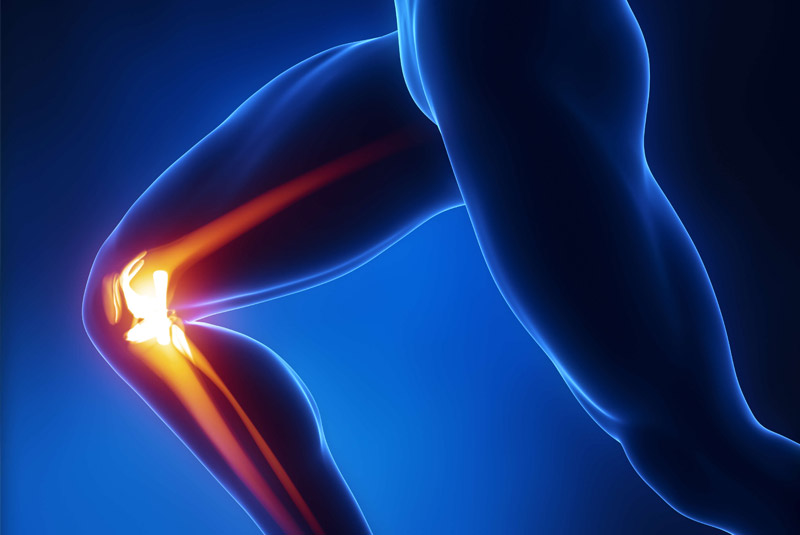

Έχει 5ετή μετεκπαίδευση και εργασία στο Ηνωμένο Βασίλειο ως ειδικός Ορθοπαιδικός Χειρουργός. Έχει εργαστεί στα Ορθοπαιδικά Τμήματα των Νοσοκομείων Southampton University Hospitals NHS Trust, Leeds Teaching Hospitals NHS Trust και στο Northampton General Hospital NHS Trust, με υποεξειδίκευση στη Χειρουργική Ώμου, Γόνατος, Ισχίου, Ποδοκνημικής & Άκρου Ποδός, Ώμου & Αγκώνος και Γενικού Τραύματος Ενηλίκων και Παίδων.

Κατά τη διάρκεια της εργασίας του στο Ηνωμένο Βασίλειο εκπαιδεύτηκε σε σύγχρονες τεχνικές Αρθροσκοπικής Χειρουργικής και Επανορθωτικής Χειρουργικής Ισχίου, Γόνατος και Ώμου. Επιπλέον έχει δώσει πολυάριθμες διαλέξεις και έχει εκπαιδεύσει νεότερους Ορθοπαιδικούς και φοιτητές Ιατρικής. Αξιοσημείωτο και πλούσιο είναι το επιστημονικό του έργο με συμμετοχή σε δεκάδες συνέδρια και σεμινάρια στην Ελλάδα και στο εξωτερικό και έχει πληθώρα προφορικών ανακοινώσεων και δημοσιεύσεων.

Παθήσεις & Θεραπείες